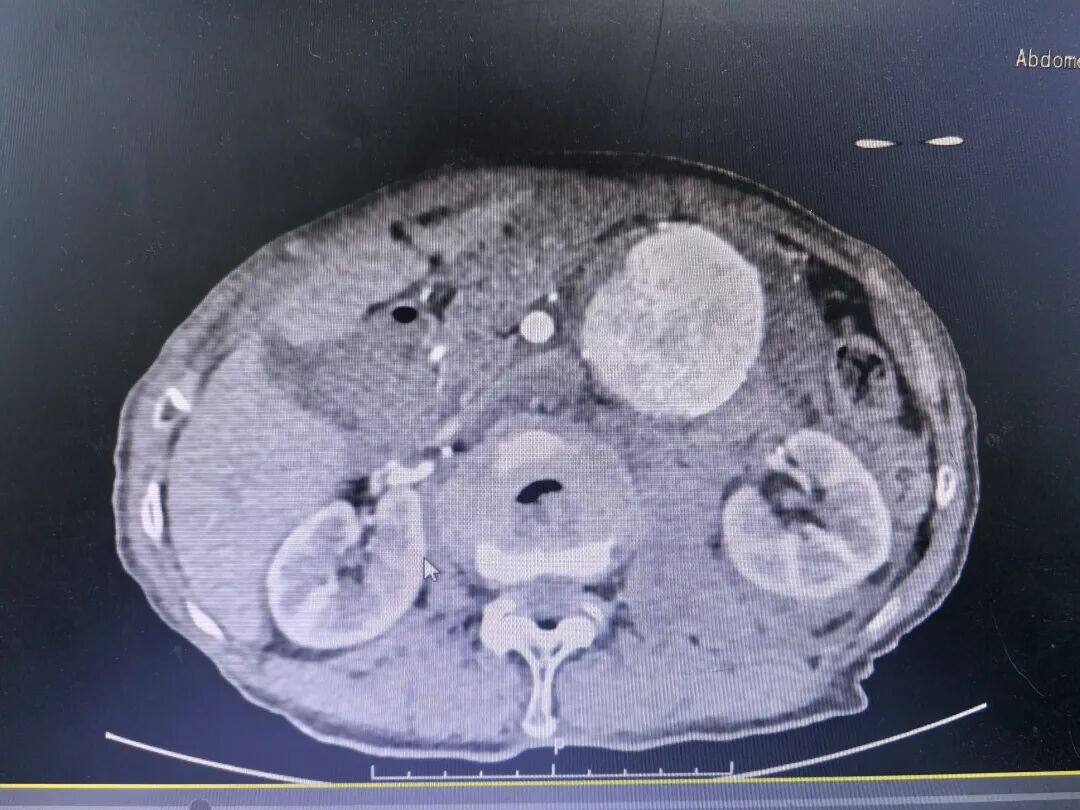

腹主动脉瘤,被称为“体内的不定时炸弹”,一旦破裂,死亡率极高。对于89岁的老人来说,这颗“炸弹”不幸被引爆。10月10日,患者因突发剧烈腹痛被紧急送入该院,经检查,确诊为腹主动脉瘤破裂出血,情况万分危急。

经过专家团队的全面评估和审慎决策,认为唯有行腹主动脉瘤腔内修复术(EVAR)才有一线生机。这是一种微创介入手术,仅需在双侧大腿根部切开约2厘米的小切口,通过股动脉将覆膜支架系统精准输送到动脉瘤部位,像搭桥一样在血管内建立起一道坚固的“屏障”,隔绝破裂的瘤腔,从而达到止血和治愈的目的。